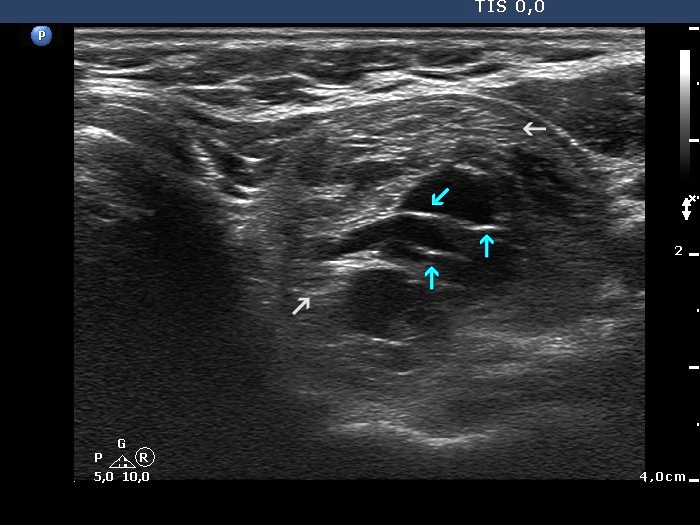

The composition of the nodule - case 653 (ultrasonographic picture 4b)

Upper part of the left lobe, transverse scan. Blue arrows point to back wall figures, lines and granules, caused by posterior enhancement. The nodule has non-specific pale echogenic figures, as well (grey arrow).